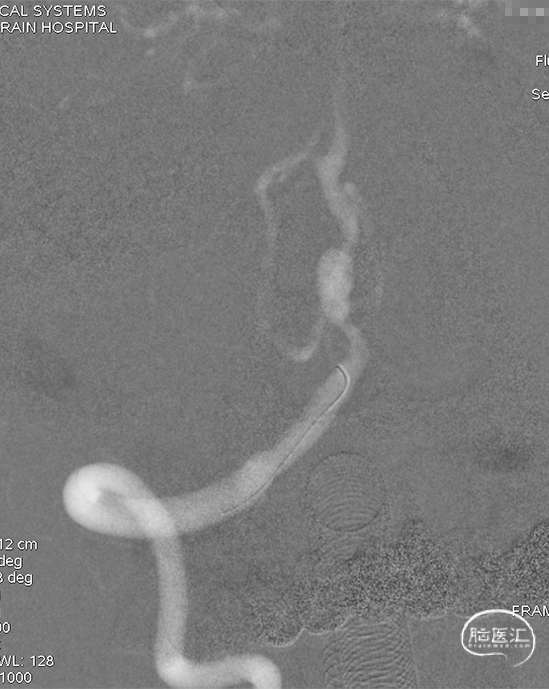

术后即刻DSA。

术后即刻稀释造影:“拉直”可见支架贴壁良好。